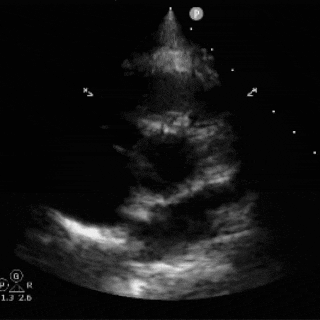

术后心超随访:心脏各房室结构及室壁厚度正常,室壁运动协调,升主动脉及肺动脉内径无异常;房间隔封堵器位置稳定,CDFI证实心房水平未见残余分流。各瓣膜形态及启闭功能正常,未探及明显反流。

超声所见:

各房室腔内径正常范围:房间隔可见封堵器强回声,位置固定;室间隔与左室后壁不厚,呈逆向运动,运动幅度正常;升主动脉内径正常,主肺动脉内径不宽。各瓣膜形态回声正常;

CDFI:房水平未见明显分流信号。心尖四腔心切面流入道呈红色血流束,流出道呈蓝色血流束;频诺多普勒显示,各瓣口均呈层流频谱。

心包腔内未见明显游离液性暗区。

超声提示:

卵圆孔未闭封堵术后

目前心内结构及功能未见明显异常